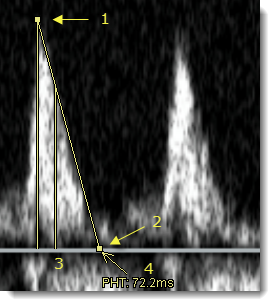

Υπολογισμός χρόνου ημίσειας πίεσης (PHT)Αριθμός θέματος: 1425412549325

Χρησιμοποιήστε το εργαλείο PHT για να υπολογίσετε τον χρόνο ημίσειας πίεσης σε εικόνες υπερηχογραφήματος Doppler.

Αυτό το εργαλείο μπορεί να χρησιμοποιηθεί μόνο σε εικόνες ή περιοχές εικόνων όπου η μονάδα κάθετης κατεύθυνσης είναι συμβατή με μέτρα ανά δευτερόλεπτα και η μονάδα οριζόντιας κατεύθυνσης είναι συμβατή με δευτερόλεπτα (Doppler US).

- Στην επάνω γραμμή εργαλείων της περιοχής εικόνας, κάντε κλικ στο βέλος δίπλα στον χάρακα για να ανοίξει η λίστα σημάνσεων και επιλέξτε.

- Κάντε κλικ στο σημείο της μέγιστης ταχύτητας (1) στην περιοχή Doppler της εικόνας υπερηχογραφήματος για να τοποθετήσετε την πρώτη λαβή της σήμανσης.

Η δεύτερη λαβή της σήμανσης εμφανίζεται αυτόματα στη γραμμή βάσης (ταχύτητα = 0 m/s).

- Μετακινήστε τη δεύτερη λαβή (2) κατά μήκος της γραμμής βάσης προς τη σωστή κατεύθυνση και κάντε κλικ για να ολοκληρώσετε τη σήμανση.

Εμφανίζεται μια κάθετη γραμμή (3) στο σημείο όπου η κλίση έχει τη μισή από τη μέγιστη αρχική τιμή της. Το PHT υπολογίζεται και εμφανίζεται σε χιλιοστά του δευτερολέπτου (4).